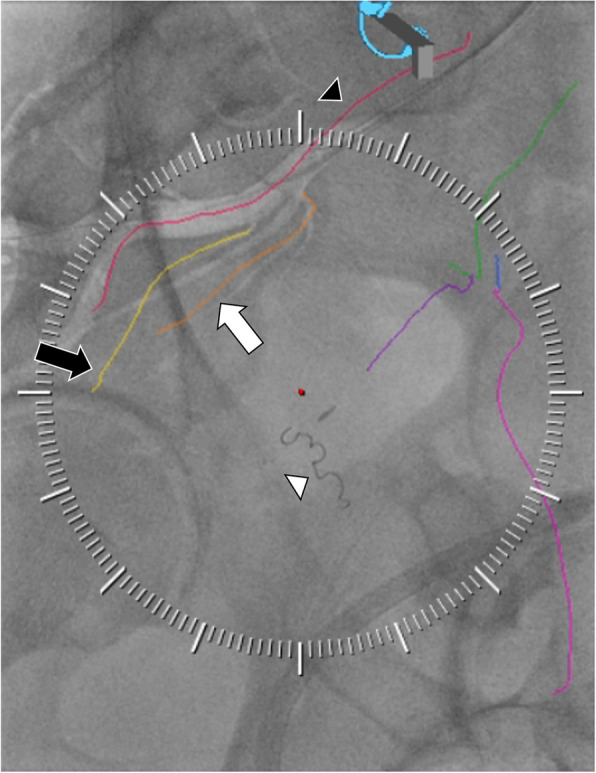

Background: Prostate artery embolization (PAE) requires a careful understanding of pelvic arterial anatomy and identifying prostatic artery variants. Pre-procedure CTA and intra-procedural cone beam CT are traditional means of planning and performing PAE, with the latter providing guidance for embolization. Photon counting detector (PCD) CT enables ultra-high spatial resolution (UHR) whole-body imaging. For PAE, we obtain a single UHR PCD CT arterial phase acquisition, which provides both detailed pre-procedure pelvic arterial anatomic information and a dataset for 2D (angiographic) to 3D (CTA) fusion for intra-procedural guidance during PAE using embolization guidance software in the angiography suite.

Case presentations: In six patients who underwent technically successful PAE via a left transradial approach, the pre-procedure diagnostic UHR pelvic PCD prostate CTA delineated bilateral prostatic artery origins and course in all cases, as confirmed with conventional angiograms. Further, registration of the UHR PCD CTA for embolization guidance was successful in all cases, augmenting vessel selection. No complication occurred.

Conclusion: UHR PCD CTA is a novel imaging technology that can provide detailed prostate arterial anatomic information for pre-procedure PAE planning. Further, this same UHR PCD CTA dataset can be used for intra-procedural embolization guidance using commercially available embolization guidance software.